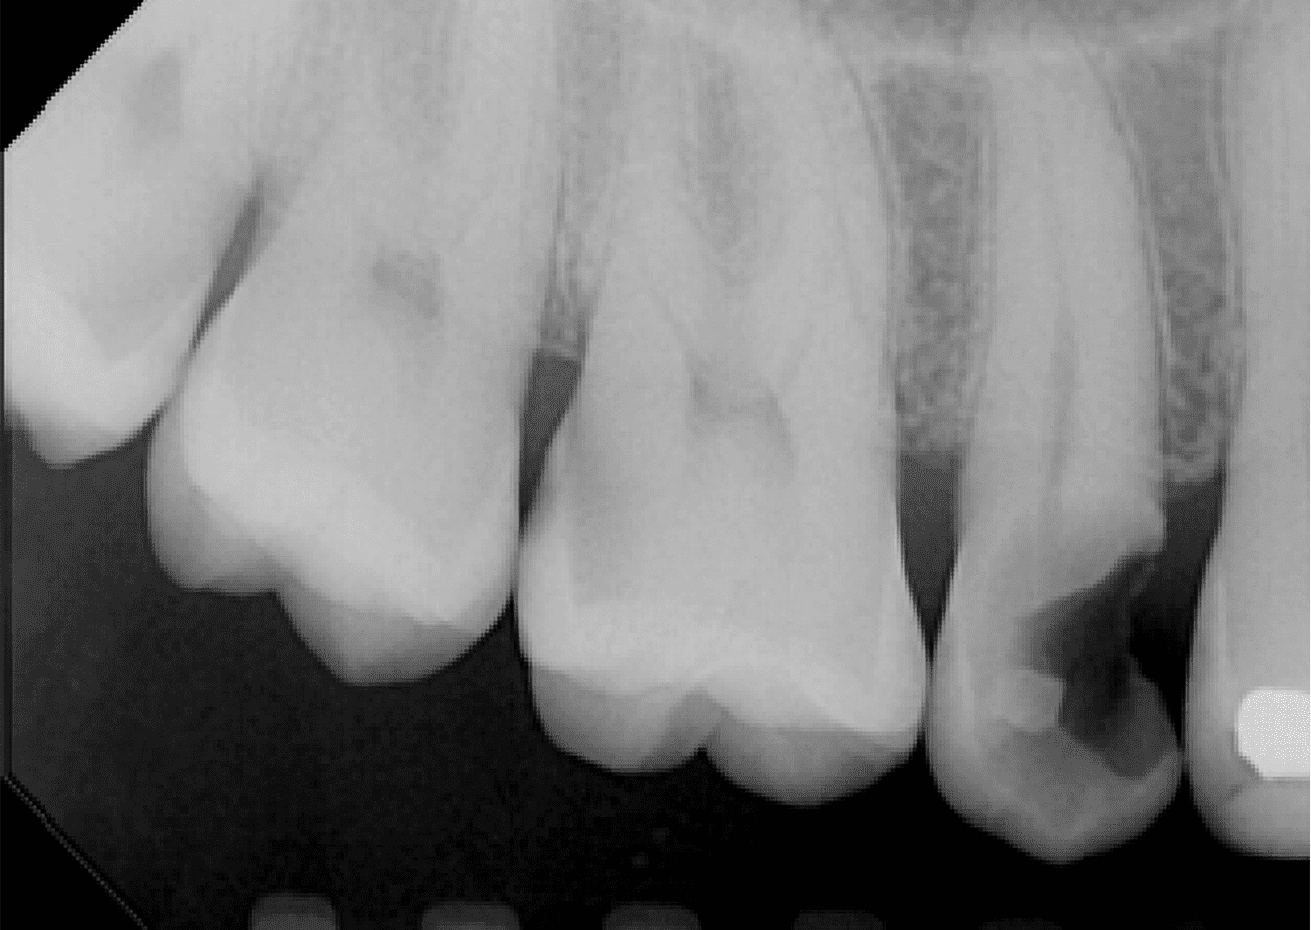

O exame clínico inicial, do dente 15, apresentava selamento provisório com ionômero de vidro e exame radiográfico apresentava alívio de 2/3 do conduto.